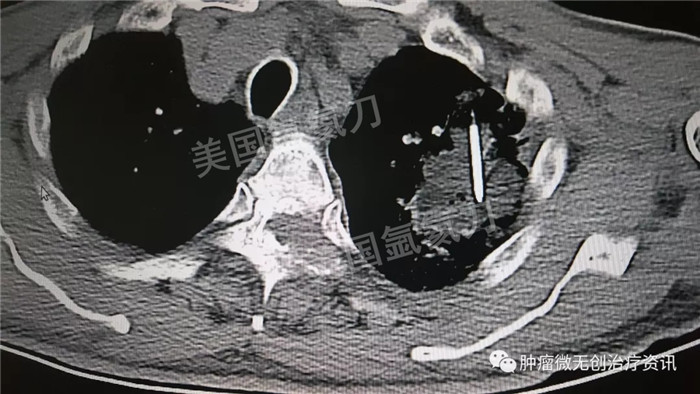

民航总医院氩氦刀冷冻消融治疗肺癌

63岁男性患者,发现左肺占位1天入院,伴多发骨转移及肺内转移,行氩氦靶向治疗减瘤,同时穿刺取病理活检。